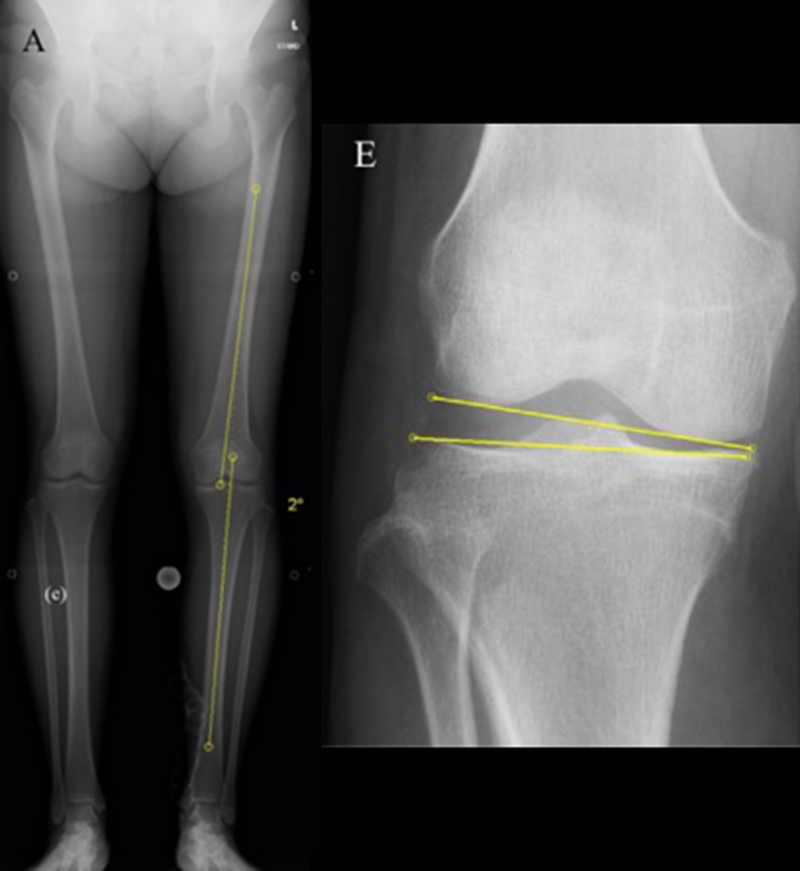

关于SONK与下肢力线的关系,一项研究结果显示SONK组MPTA畸形比OA组更大,高达约1.5°,SONK组JLCA也显著高于OA组。

提示胫骨近端内翻畸形和膝关节松弛,有助于诱发SONK,SONK骨软骨病变的大小受胫骨近端内翻畸形的影响。临床中MPTA小于 84°且伴有急性膝关节疼痛应尽快MRI检查。

国内一项研究纳入内侧半月板损伤患者97例,男40例,女57例,年龄32~66岁,通过MRI测量半月板外突>3mm者38例,无半月板外突者59例。膝内翻患者半月板突出的发生率为89%,半月板根部撕裂患者半月板突出的发生率为78%,证明膝内翻、内侧半月板根部撕裂是造成内侧半月板突出的主要危险因素。

膝内翻 内侧半月板根部撕裂

应力源性理论